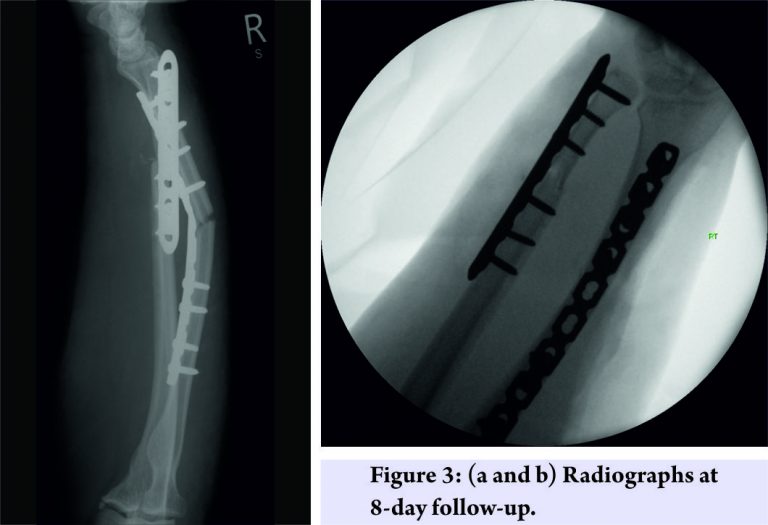

Since the patient was dependent on her upper limb to mobilize and transfer weight, we felt that it was important to stabilize the forearm contrary to usual practice. Therefore, the patient was listed for an open reduction and fixation of both the radius and ulna. Intraoperatively, the radial fracture was found to be simple with little comminution. A ten-hole locking compression plate was selected with a reasonable working length and then contoured to respect the radial bow. The ulnar fracture was found to be comminuted with rounding of the fracture ends, suggesting that this had been partially fractured for some time, indicative of a fatigue fracture. Fixed-angle (locking) plates on both radius and ulna were used to minimize the risk of construct failure through implant cut-out, about which the patient would be unaware owing to her lack of sensibility in the arm.Bone samples from the fracture site were sent for histology to exclude malignancy, although this seemed unlikely from the macroscopic appearance of the fracture site. Further, the distal radioulnar joint was found to be stable, and the radiographs (Fig. 2) were satisfactory.

Despite fracture fixation, it was found in the initial follow-up clinic, 8 days later, that the construct had failed. Radiographs showed that the radial plate had flexed and the deformity was approximately 30° (Fig. 3). Both wounds had also dehisced, due to the tension, they were under post-operatively. 5 weeks later, after satisfactory wound healing, a stronger bespoke radial plate was ordered, and the construct failure was successfully revised. The new construct was an eleven plus four hole volar rim plate pre-contoured into extension at the fracture site. It was protected in the immediate post-operative period with external casting in addition to the internal fixation (Fig. 4). 10 months after the revision, the patient has reported no further problems, the X-rays are progressing to union satisfactorily, and the patient has a good range of movement including forearm rotation despite heterotopic ossification in the interosseous membrane (Fig. 5).